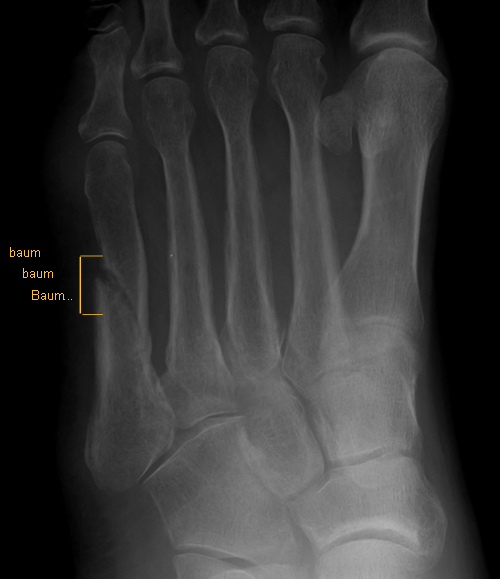

When she returned to the room her tone had changed and she was all concerned about me again when she showed me the images. "Here is where your fracture is still active," she said "and in fact this one area looks perhaps a little worse than the first image".

As I was viewing the image over her shoulder I could definitely see what she was talking about and felt a sinking feeling come over me. Not only was this not evidence of a superior healing, it was a sign of (baum, baum, Baum... (hopefully you recognize this as that dramatic music sound effect from various crime dramas of the 50s)) Delayed Healing.

I however had a (baum, baum, Baum...) MID-SHAFT - 5th metatarsal fracture. He paused dramatically after saying this. He said these type of fractures are the slowest to heal due to (long list of reasons) and basically went on to outline that I would be lucky to have this all over with by 6 months or more. He also said that x rays were not the best evidence of healing (so why did I have another one???) and after squeezing my foot and watching me flinch he said I would not be feeling that kind of pain if my bone was ready for weight bearing. (I personally was certain I would not be feeling that kind of pain if someone had not squeezed my foot, but apparently this too was part of the whole 'healing process'.)